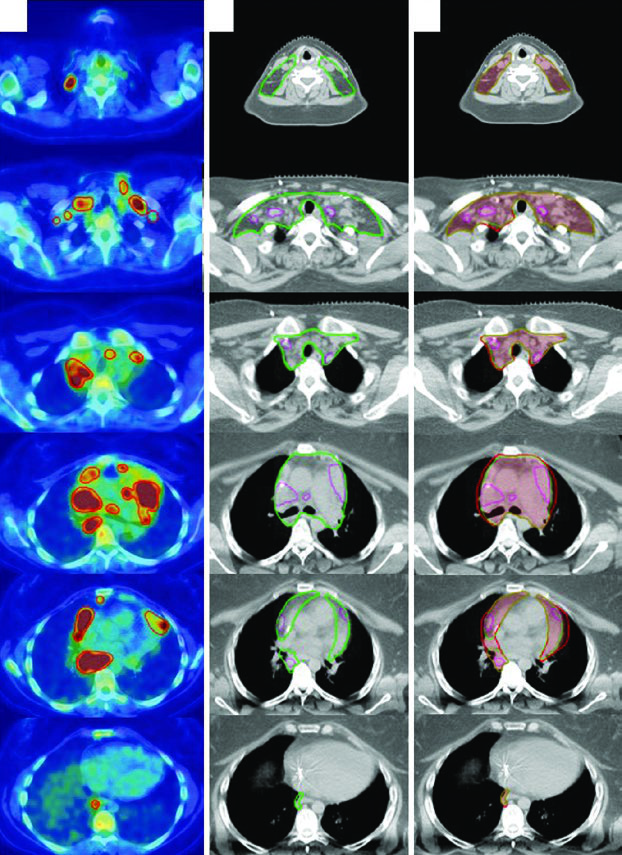

LH Nodular de Predominância Linfocitária (NLPHL)

Um homem de 61 anos com NLPHL estádio IIA envolvendo linfonodos supraclavicular direito, subpeitoral e axilar foi tratado com RT definitiva isolada. Simulado com braços elevados em wingboard. O PET diagnóstico foi fusionado à CT de simulação. Como a RT foi modalidade única (sem quimioterapia), margens de CTV mais generosas foram necessárias para cobrir potencial doença subclínica.

DLBCL de Cabeça e Pescoço

Uma mulher de 47 anos com DLBCL estádio IIA de tonsila esquerda e pescoço esquerdo (nível 2, 5,6 cm) recebeu 3 ciclos de R-CHOP seguidos de RT consolidativa. Simulada com pescoço em extensão, imobilizada com máscara aquaplast de 5 pontos. O CTV ISRT cobre toda a tonsila esquerda e o nível ganglionar envolvido, incluindo 1–2 cm superior e inferior à extensão pré-quimioterapia. Casos de linfoma de cabeça e pescoço exigem atenção especial ao registro entre PET diagnóstico e CT de simulação.